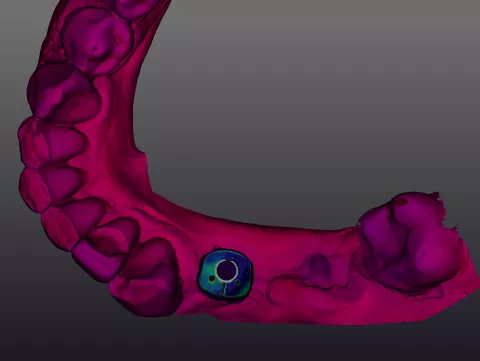

13a. 13b. 13c. The intraoral scan was processed to generate a 3D digital model for prosthetic design.

13a

13b

13c

14a. 14b. 14c. 14d. 14e. Exocad® prosthetic design based on the intraoral scan and implant position.

14a

14c

14d

14e